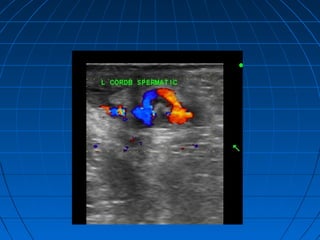

Xoắn tinh hoànXoắn tinh hoàn

Xoắn tinh hoàn gây nghẽn các mạchXoắn tinh hoàn gây nghẽn các mạch

máu nuôi ( 3 đm tận) thương tổnmáu nuôi ( 3 đm tận) thương tổn

không hồi phục nếu sau 4-6hkhông hồi phục nếu sau 4-6h

Hai lứa tuổi hay gặp là sơ sinh và sauHai lứa tuổi hay gặp là sơ sinh và sau

dậy thì, tần suất tăng 10 lần nếu códậy thì, tần suất tăng 10 lần nếu có

kèm tinh hoàn ẩnkèm tinh hoàn ẩn

Lâm sàng : đau sưng vùng bìu khôngLâm sàng : đau sưng vùng bìu không

kèm sốtkèm sốt

 dấu hiệu trực tiếp: thừng tinh bịdấu hiệu trực tiếp: thừng tinh bị

xoắn, còn mạch hoặc vô mạchxoắn, còn mạch hoặc vô mạch

 Dấu hiệu gián tiếp: tinh hoàn màoDấu hiệu gián tiếp: tinh hoàn mào

tinh hoàn tăng kích thước, hồi âmtinh hoàn tăng kích thước, hồi âm

không đồng nhất, dịch trong bao tinhkhông đồng nhất, dịch trong bao tinh

hoàn, tinh hoàn nằm cao và ra trướchoàn, tinh hoàn nằm cao và ra trước

 Giai đoạn muộn tinh hoàn vô mạch ,Giai đoạn muộn tinh hoàn vô mạch ,

có vùng hoại tử..có vùng hoại tử..